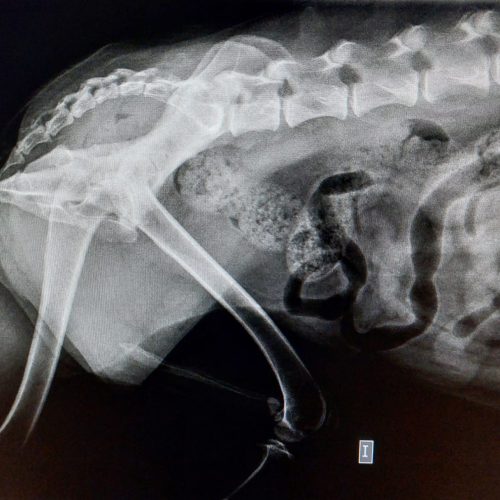

Diagnóstico por imagen

La tecnología es una aliada clave en la medicina veterinaria. Disponemos de radiología digital, ecografía especializada y endoscopia para obtener imágenes precisas y de alta calidad que nos permiten detectar, valorar y seguir la evolución de múltiples patologías con rapidez y fiabilidad.